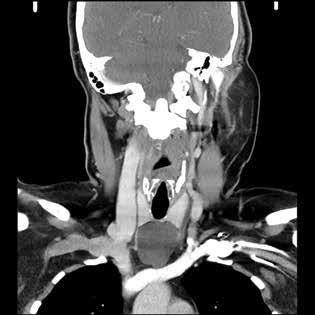

Computed tomography (CT) of the neck with intravenous contrast revealed a cystic mass of similar dimensions adhering to the anterior tracheal surface

and occupying the space between the thyroid isthmus and the aortic arch. Because of mass effect, there was splaying of the inferior poles of the thyroid lobes and the left and right innominate veins (figure 1).

A B

Figure 1. A: Axial CT with contrast of the neck and chest demonstrates a homogeneous cystic lesion overlying the inferior border of the thyroid gland, anterior border of the trachea, and the great mediastinal vessels. B: Coronal CT of the cyst demonstrates its cervical and mediastinal components with splaying of the innominate veins.